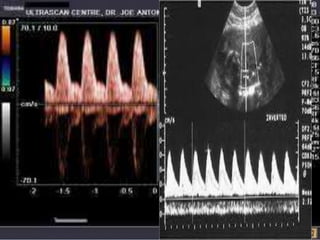

• DOPPLER OF THE UMBILICAL ARTERY

• Reduced end diastolic flow.

• Absent end diastolic flow

• Reversed end diastolic flow( severe cases)

• 112.

• DOPPLER OFTHE UMBILICAL ARTERY • Reduced end diastolic flow. • Absent end diastolic flow • Reversed end diastolic flow( severe cases)